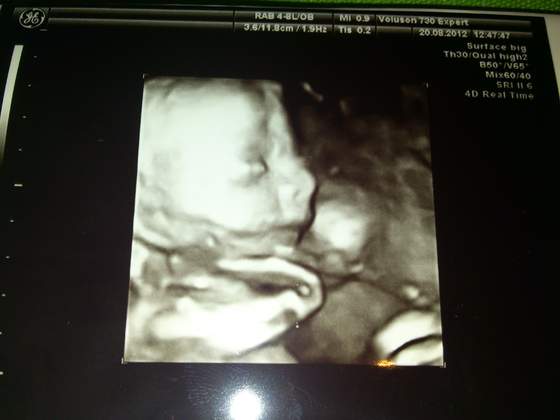

Wizytę miałam dzisiaj -> wszystko w porządku, lekarz nie miał żadnych zastrzeżeń i możecie się przywitać z PAULINKĄ